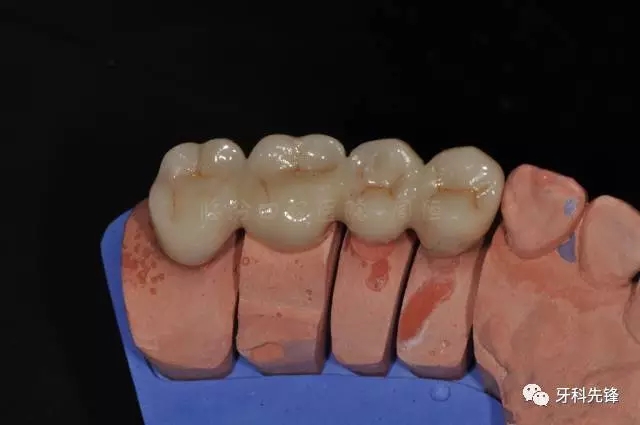

圖25烤瓷冠頜面觀

640.webp (29).jpg